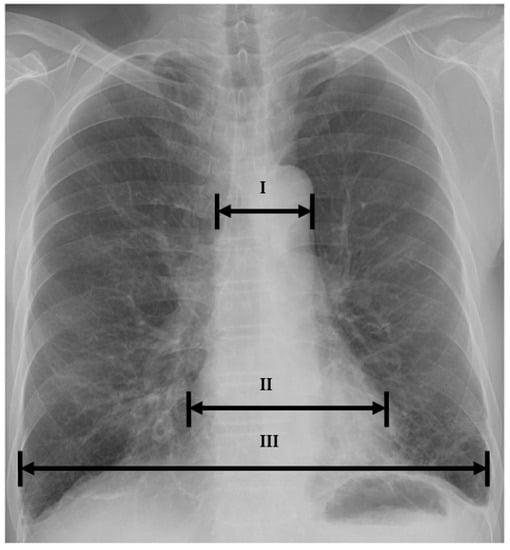

| I | Cardio-thoracic ratio | 0.51 ± 0.08 | 0.51 ± 0.06 | 0.064 |

| Mediastinal-thoracic ratio | 0.27 ± 0.05 | 0.23 ± 0.03 | <0.001 | |

| Mediastinal-cardiac ratio | 0.50 ± 0.08 | 0.45 ± 0.05 | <0.001 | |